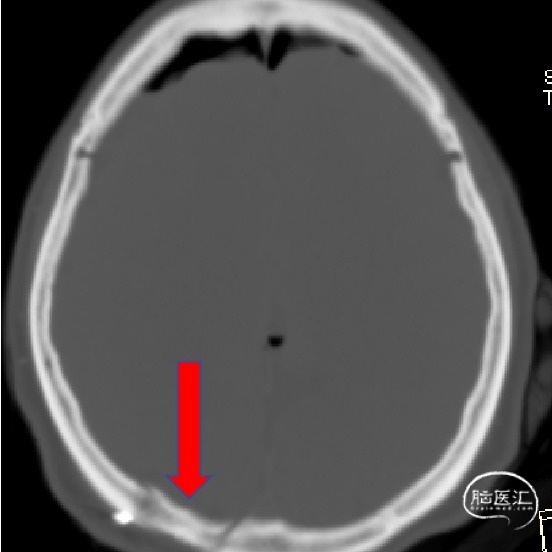

外院影像考虑脑膜瘤?室管膜瘤?

诊断:1.颅内占位性病变(左侧侧脑室三角区,脑膜瘤)2.高血压

术前情况

2023.04.21外院MR

1.结合病史体征及辅助检查诊断左侧侧脑室三角区脑膜瘤明确;